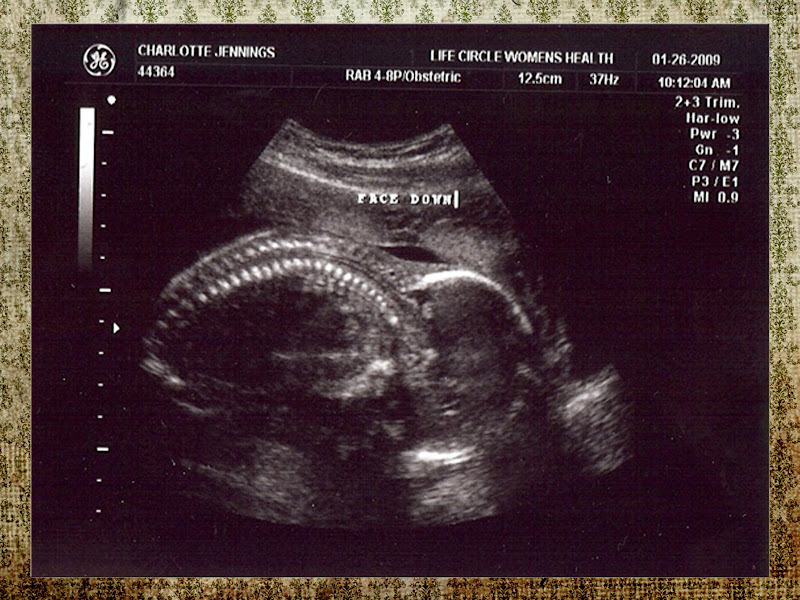

Check out our little one at 21 weeks… and his/her LONG leg!! Definitely inherited those from Daddy :O) The baby stretched out for a split second and the ultrasound tech was able to freeze the image for us. How SWEEEEEEEET!

Whoa the leg shot is super cool, Charlotte! Such a great angle!